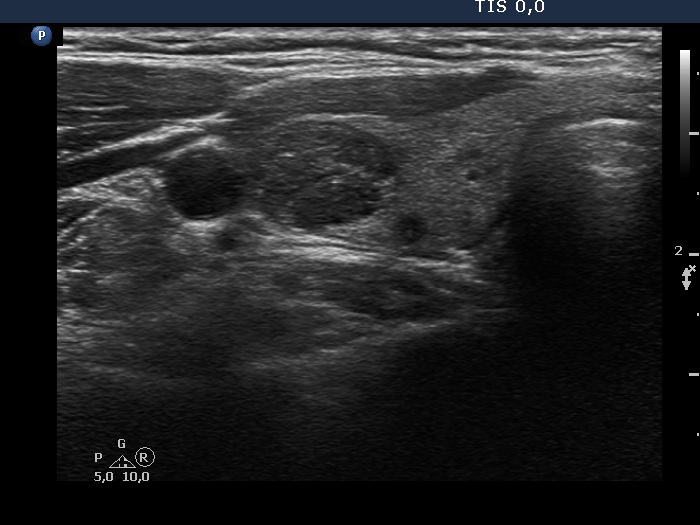

Ultrasonography. The thyroid was echonormal. Beside several hypoechoic and cystic lesions without any clinical significance, both lobes had a hypoechoic nodule. The presentation of them was very similar, both had echogenic granules and showed peripheral vascularity. However, the echogenic figures in the right nodule were probably back wall figures while those in the left nodule were microcalcifications. Regarding the vascularity, the left nodule showed perinodular blood flow while the right did not.